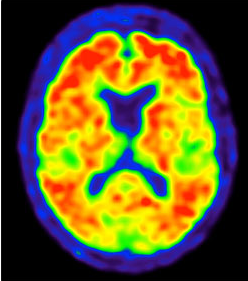

Le nouveau traitement, qui sera commercialisé par l'entreprise pharmaceutique Eisai sous le nom de Leqembi, est désormais recommandé par l'Agence américaine des médicaments (FDA) pour les patients n'ayant pas encore atteint un stade avancé de la maladie. Le Leqembi, dont le principe actif est nommé lecanemab, cible les dépôts d'une protéine appelée bêta-amyloïde. Si la cause de la maladie d'Alzheimer reste mal comprise, les malades présentent des plaques amyloïdes dans leur cerveau, qui se forment autour de leurs neurones et les détruisent à terme. C'est ce qui cause les pertes de mémoire caractéristiques de la maladie. L'autorisation de la FDA s'appuie sur les résultats d'essais cliniques ayant montré que le médicament permettait de réduire les plaques amyloïdes.